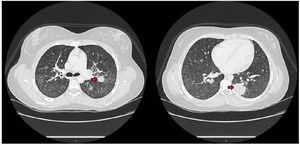

During the first 24h of hospitalization, she developed an episode of chest pain and sudden dyspnea, prompting urgent D-dimer levels to be measured (6.834ng/mL). A pulmonary artery CT angiogram revealed alveolar consolidations with the “reverse halo sign” in a peribronchovascular distribution, generalized increased density of lung parenchyma with a “tree-in-bud” pattern affecting the small airways (Fig. 1). In light of these findings, an initial analytical study was completed, including tests for autoimmunity, with negative ANA and ENA, and positive c-ANCA. The latter showed specificity for anti-proteinase-3 (PR-3) at a titer of 109UI/mL. Complement levels were normal (C3 160mg/dL and C4 29.3mg/dL), and despite normal renal function and urine analysis, a 24-h urine biochemical study was requested, revealing proteinuria levels of 3080mg/dL. Furthermore, a fiber-optic bronchoscopy was performed to better characterize the etiology of the lesions, revealing hematic crusts in both nasal vestibules and bleeding in the upper airways without signs of alveolar hemorrhage. The analysis of bronchoalveolar fluid was compatible with normality.

Coexistence of renal disease in FD and AAVThe association of FD and vasculitis is extremely rare, with only five cases of similar characteristics found in the literature, of which only one was associated with AAV. FD and AAVs (granulomatosis with polyangiitis – GPA, eosinophilic granulomatosis with polyangiitis – EGPA, and microscopic polyangiitis – MPA) can affect the kidneys, heart, central or peripheral nervous system, and lungs, with the most significant manifestations being renal involvement.5,6 Beyond the academic classification of AAVs, the genetic component and characterization of ANCA are crucial, as it has been documented that patients with anti-MPO and anti-PR3 have different genotypes that correlate better with the specificity of the ANCA antibody than with the histological classification of vasculitis itself. Another important aspect in this clinical scenario of coexisting FD and AAV is to discern whether the organ involvement, especially at the renal level, is compatible with one entity or another, posing a significant diagnostic and therapeutic challenge.6 The renal manifestations of AAV include necrotizing glomerulonephritis without glomerular immune deposits (also referred to as “pauci-immune”), crescents in more than 50% of glomeruli, and often a rapidly progressive course. In our patient's case, not only was the vasculitic component present at the renal level, but it also manifested at the pulmonary level with findings such as pulmonary nodules with the reverse halo sign and a tree-in-bud pattern affecting the small airways (Fig. 1).6–11 Delving into the pathophysiological aspects of the condition, it has been established that vasculitis can be preceded by multiple triggers, ranging from various infectious agents to their relationship with different drugs. All of this can determine the development of immunological mechanisms that initiate a systemic inflammation mediated by autoantibodies.6 The most significant immunological mechanisms involved are molecular mimicry, autoantigen complementarity, and epitope conformation, although, specifically, vasculitis with PR-3 specificity responds to humoral and cellular components. In the same vein, the role of extracellular traps from neutrophils (NETs) containing MPO (or PR-3) and DNA in a network of histones/chromatin is being investigated. While their primary function is beneficial for combating infections by providing a crucial innate immune mechanism, excessive NET release has been associated with numerous diseases through their effector action of neutrophil-mediated damage, allowing them to circulate, present antigens to the immune system, promote hypercoagulability, and activate the alternative pathway of complement.10 NETs are also being investigated as a pathogenic determinant in FD, playing an important role in the context of ischemic cerebrovascular involvement in these patients. The neutrophil participates in innate immunity processes and plays a fundamental role in the pathophysiology of AAV, specifically in GPA. The accumulation of glycosphingolipids may increase neutrophil survival, exacerbating its pathogenic power at the level of blood vessels and favoring the process of immune-mediated vascular damage. This has been evidenced in our patient with a sluggish renal evolution despite the establishment of appropriate treatment and the occurrence of deep vein thrombosis precipitated by an endovascular catheter, favored by a pro-coagulant inflammatory environment.5,10